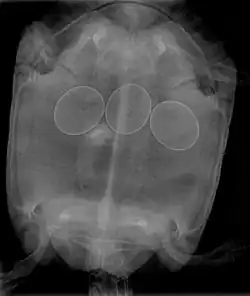

Ce symptôme est particulièrement surveillé par les aviculteurs et par les éleveurs d'oiseaux ou de tortues de compagnie. C'est une manifestation subjective de nombreuses maladies, de carences ou de malformation d'œufs. Les femelles présentent un abdomen gonflé et deviennent amorphes et anorexiques.

Tortue

L'ocytocine et le gluconate de calcium sont utilisés[2].